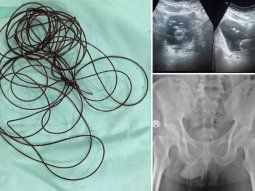

Caso insólito en Indonesia Un hombre se introdujo una cuerda de dos metros por el pene para aumentar su placer sexual Indonesia